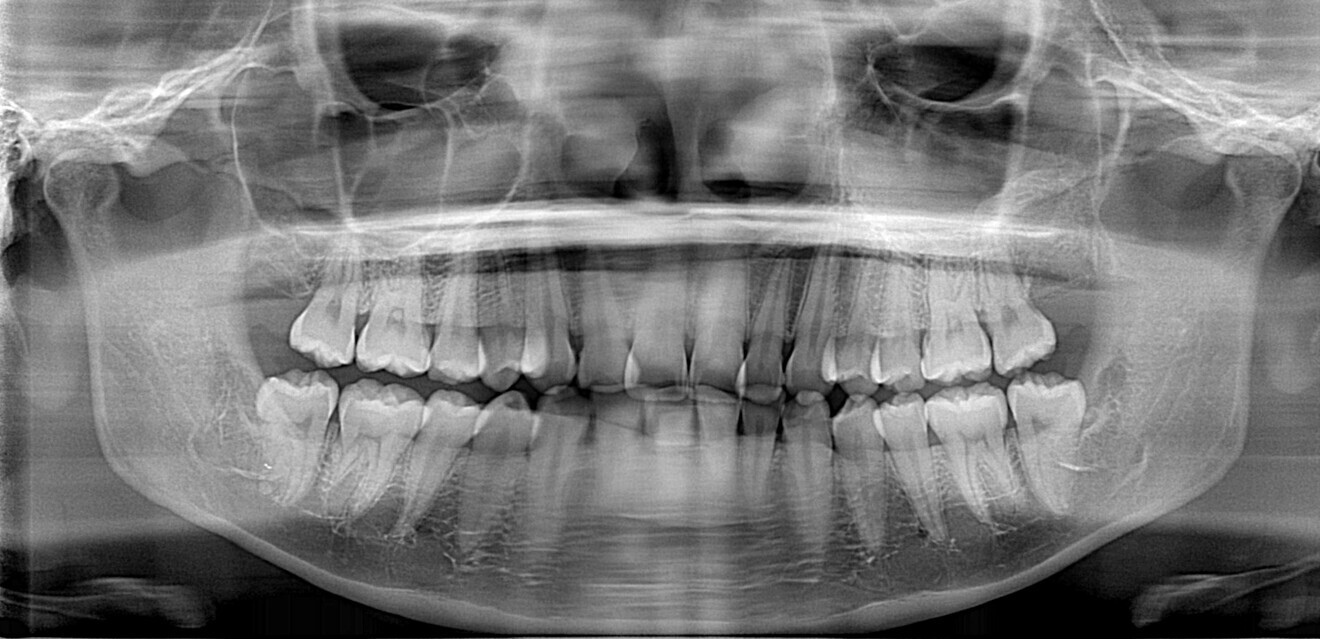

Fig. 4

The starting point for Oratomic4D was selecting a real patient to replicate. After an extensive search, the patient, Tina, was chosen for her ideal oral anatomy and range of treatments that could be simulated. Unlike a typodont model, Tina had mild crowding, impacted maxillary and mandibular third molars, and complex root canal anatomy (Figs. 2–7).

These irregularities in Tina’s oral anatomy made her an ideal candidate for the creation of a range of realistic simulation models that are highly representative of the types of patients encountered in dental practice.

Combining Tina’s intra-oral scans and CBCT data along with Oratomic4D’s internal design and manufacturing processes, the company was able to accurately replicate her jaws, bone structure, ligaments, teeth and root canals on a 1:1 scale using Asiga printers.